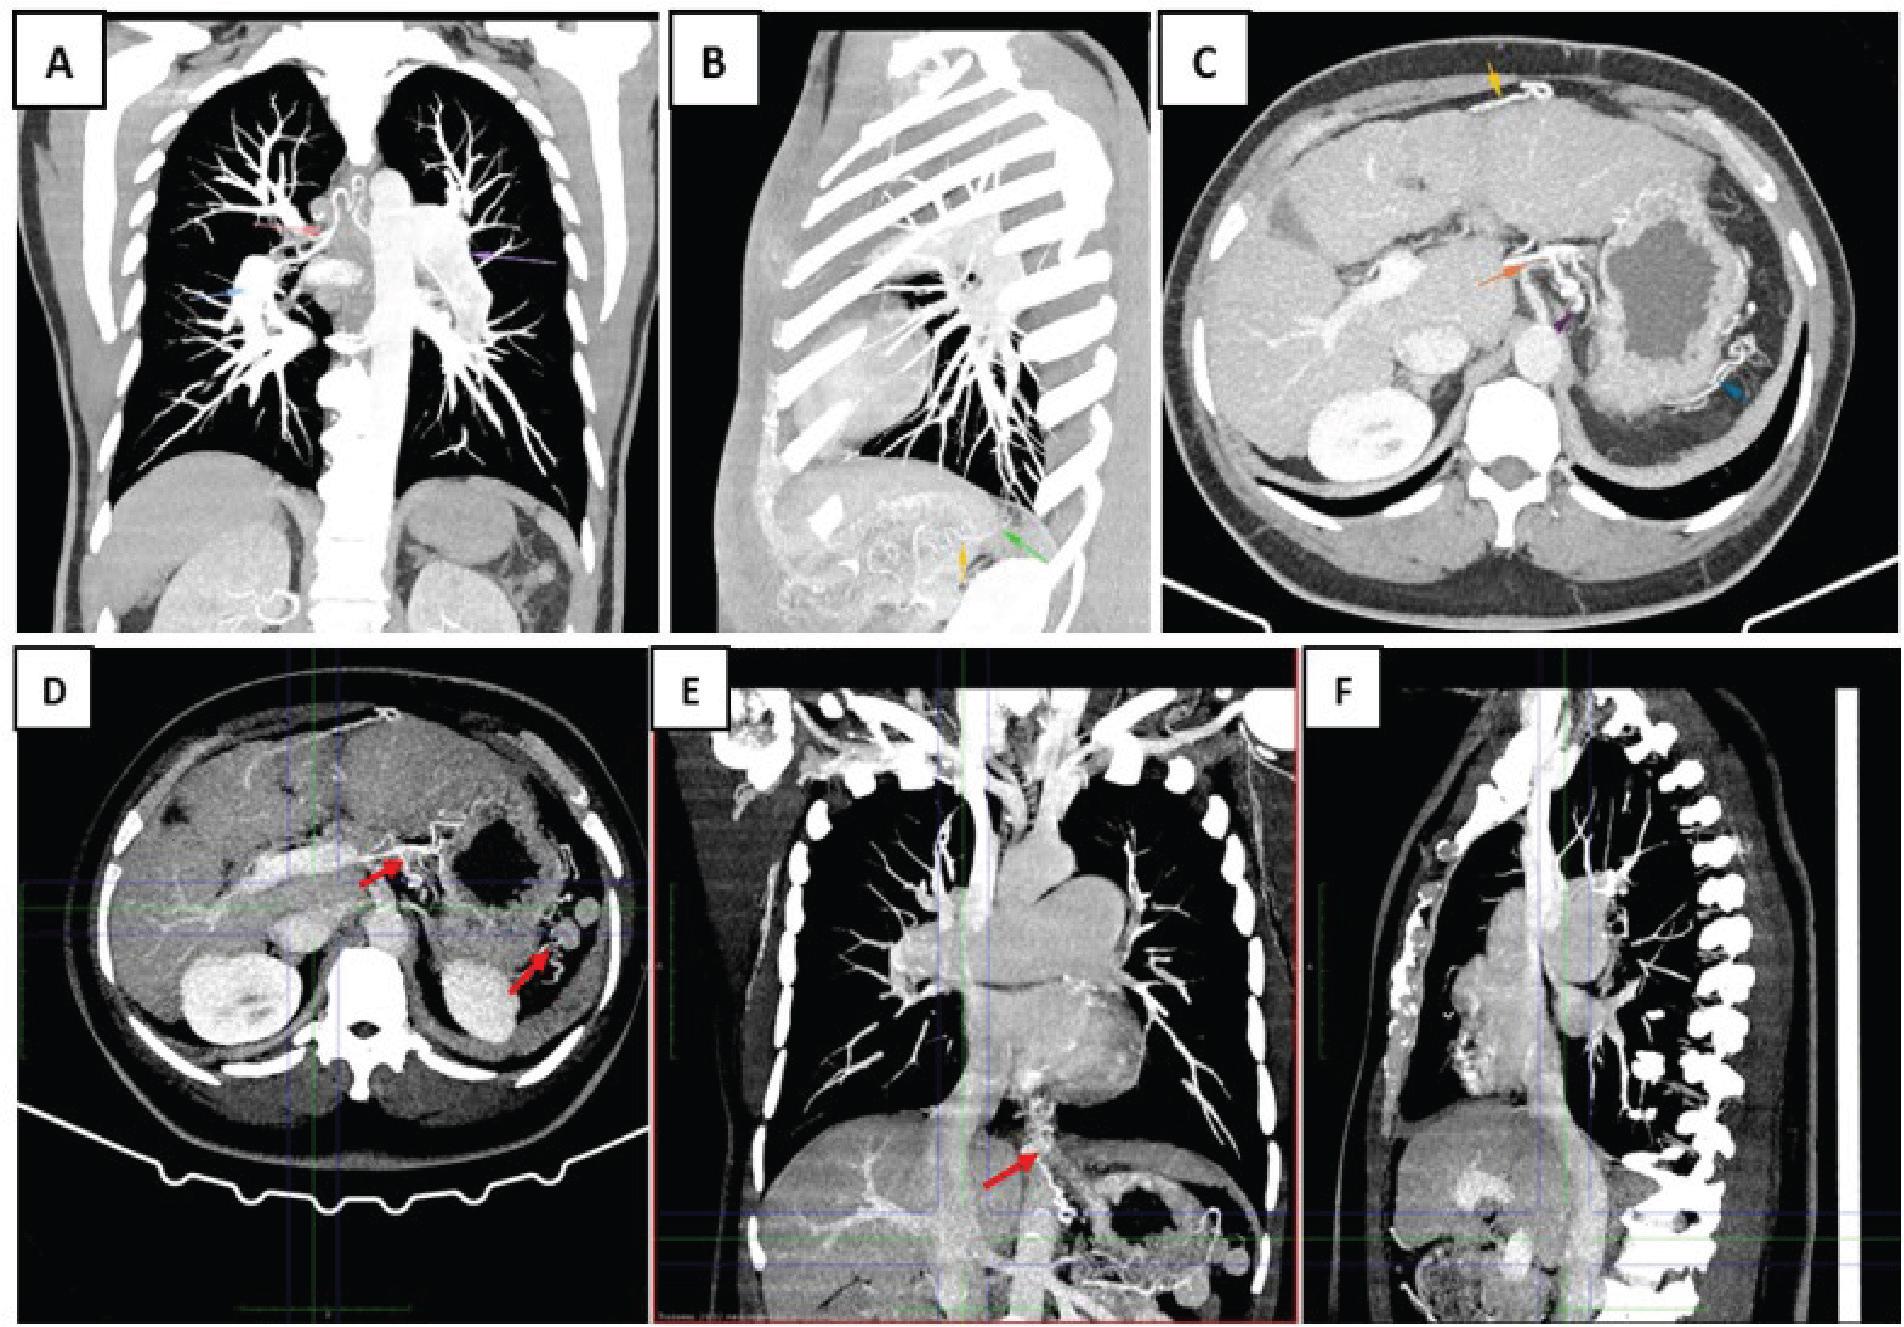

The pathophysiologic mechanisms of PH development are linked to the formation of portosystemic collateral circulation, which seems to act as an adaptive mechanism in the initial stage, leading to the evolution of PH (Figures 3A–3E). Portosystemic shunts significantly contribute to the genesis of PH by carrying elevated levels of vasoactive and inflammatory mediators, such as endothelin-1, serotonin, nitric oxide and pro-inflammatory cytokines, that are normally metabolised by the liver in the pulmonary circulation. This promotes haemodynamic stress and initiates a cascade of pathological vascular remodelling. In this way, a chronic liver disease evolves into a complex and potentially lifethreatening cardiopulmonary disorder, ultimately leading to PoPH (17).

MIP reconstructions (coronal, sagittal, axial planes) showing multiple dilated portosystemic collateral vessels. (A) Coronal CT image showing dilatation of the pulmonary arteries (blue and purple arrows) and hypertrophy of the bronchial arteries (red arrow), as part of the compensatory mechanism associated with PoPH. (B) Sagittal reconstruction highlighting the trajectory of collateral venous circulation in portosystemic shunting pathways; (C) Axial abdominal CT reconstruction illustrating a cirrhotic liver with a nodular contour and irregular hepatic surface. Note the dilated portal vein (red arrow) and the partially visualised recanalised paraumbilical vein (yellow arrow), suggestive of PHT. (D–F) MIP reconstruction (axial, coronal, and sagittal) highlights the pulmonary arterial arborisation and extensive abdominal collateral vessels. Aberrant ascending venous pathways, likely originating from perioesophageal and diaphragmatic networks, suggest portopulmonary collateral formation potentially involved in localised pulmonary congestion or haemoptysis. MIP, maximum intensity projection; PHT, portal hypertension; PoPH, portopulmonary hypertension.

Thick-slab maximum intensity projection (MIP) reconstructions revealed extensive and tortuous portosystemic collateral vessels, particularly in the perigastric, retrogastric, peripancreatic and retroperitoneal regions, consistent with long-standing PHT in a post-splenectomy setting. Notably, multiple aberrant vascular pathways were observed tracking along the diaphragmatic and perioesophageal axes, some of which appeared to ascend towards the lower mediastinum and peribronchial territories (Figures 3D and 3E).

These findings raised the suspicion of portopulmonary vascular collaterals – a rarely described phenomenon in advanced PoPH. Although such abnormal connections are not visible on bronchoscopy, they may be identified on CT angiography or MRI (20, 21) and are thought to arise from perioesophageal or diaphragmatic networks that anastomose with small pulmonary vessels. These pathways may expose the pulmonary circulation to unfiltered portal blood, potentially leading to localised congestion, angiodysplastic lesions or microvascular shunting (22). Occasionally, such collaterals may become varicose, increasing the risk of haemoptysis by weakening the vascular wall under elevated pressure (23). In our patient, the imaging suggested the presence of possible vascular structures in the right lower lobe, where the bleeding occurred, raising the suspicion of portopulmonary shunting (Figures 3A and 3F). However, in the absence of angiographic confirmation, this remains a plausible but unproven hypothesis.